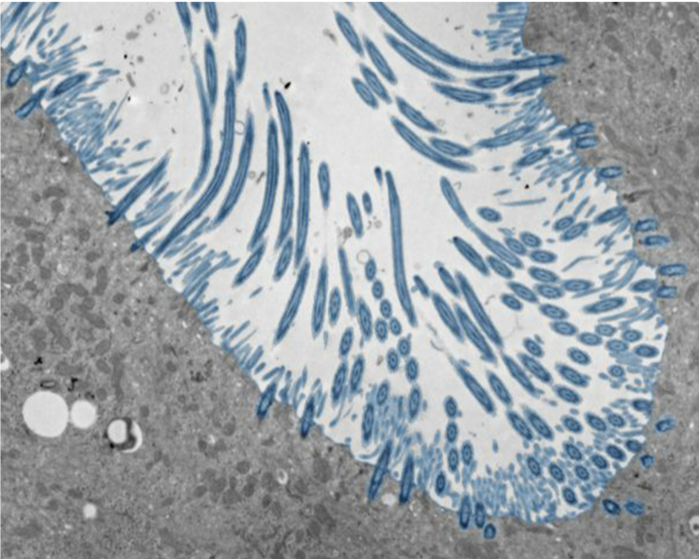

| ▲ 이 전자 현미경 이미지는 오가노이드 내 인간 비강 상피 세포의 섬모를 파란색으로 보여준다. © Julien Amat & Bao Wang |

이러한 조건에서 줄기세포는 인간 비강과 기도의 점막에서 흔히 발견되는 다양한 세포 유형으로 구성된 조직으로 분화했다. 여기에는 점액을 생성하는 세포와 폐에서 점액을 제거하는 섬모 세포 등이 포함된다. 하지만 실제 코와는 달리, 오가노이드에는 면역 세포가 존재하지 않았다.